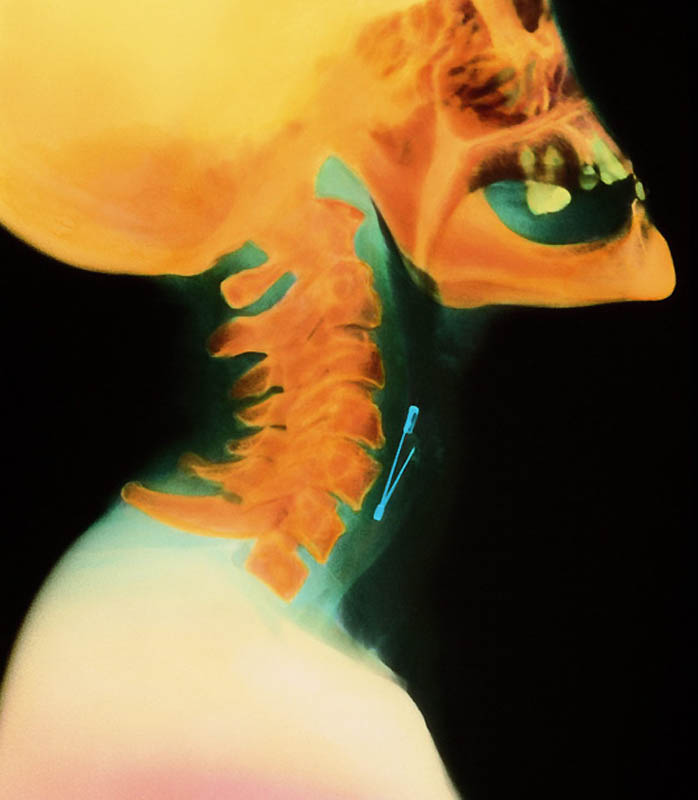

Булавка в горле женщины